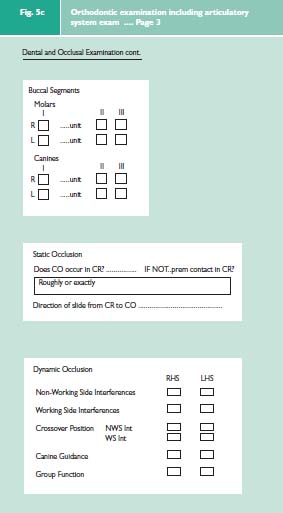

It is important to emphasise that it is necessary to carry out a full occlusal examination for all orthodontic patients. It is essential to record not only the patient’s habitual bite (centric occlusion CO or intercuspation position ICP) but also to record the patient’s ideal jaw relationship (centric relation = CR or retruded contact position = RCP). This is done against the benchmark of ‘ideal occlusion’.1 Firstly does CO occur in CR? If not, what is the discrepancy between the two? Secondly does the anterior guidance on the front teeth occur with an absence of posterior interferences?

The three elements of an examination of the articulator system2 can easily be incorporated into an orthodontic examination protocol (Fig. 5a–c). This comprehensive examination is divided into two main parts. The jaw and facial examination will record the pattern of the skeletal bases and the facial symmetry, the condition of the TMJs and mandibular muscles, and the soft tissue characteristics. The dental and occlusal examination will record the position of the teeth and their occlusal contacts.